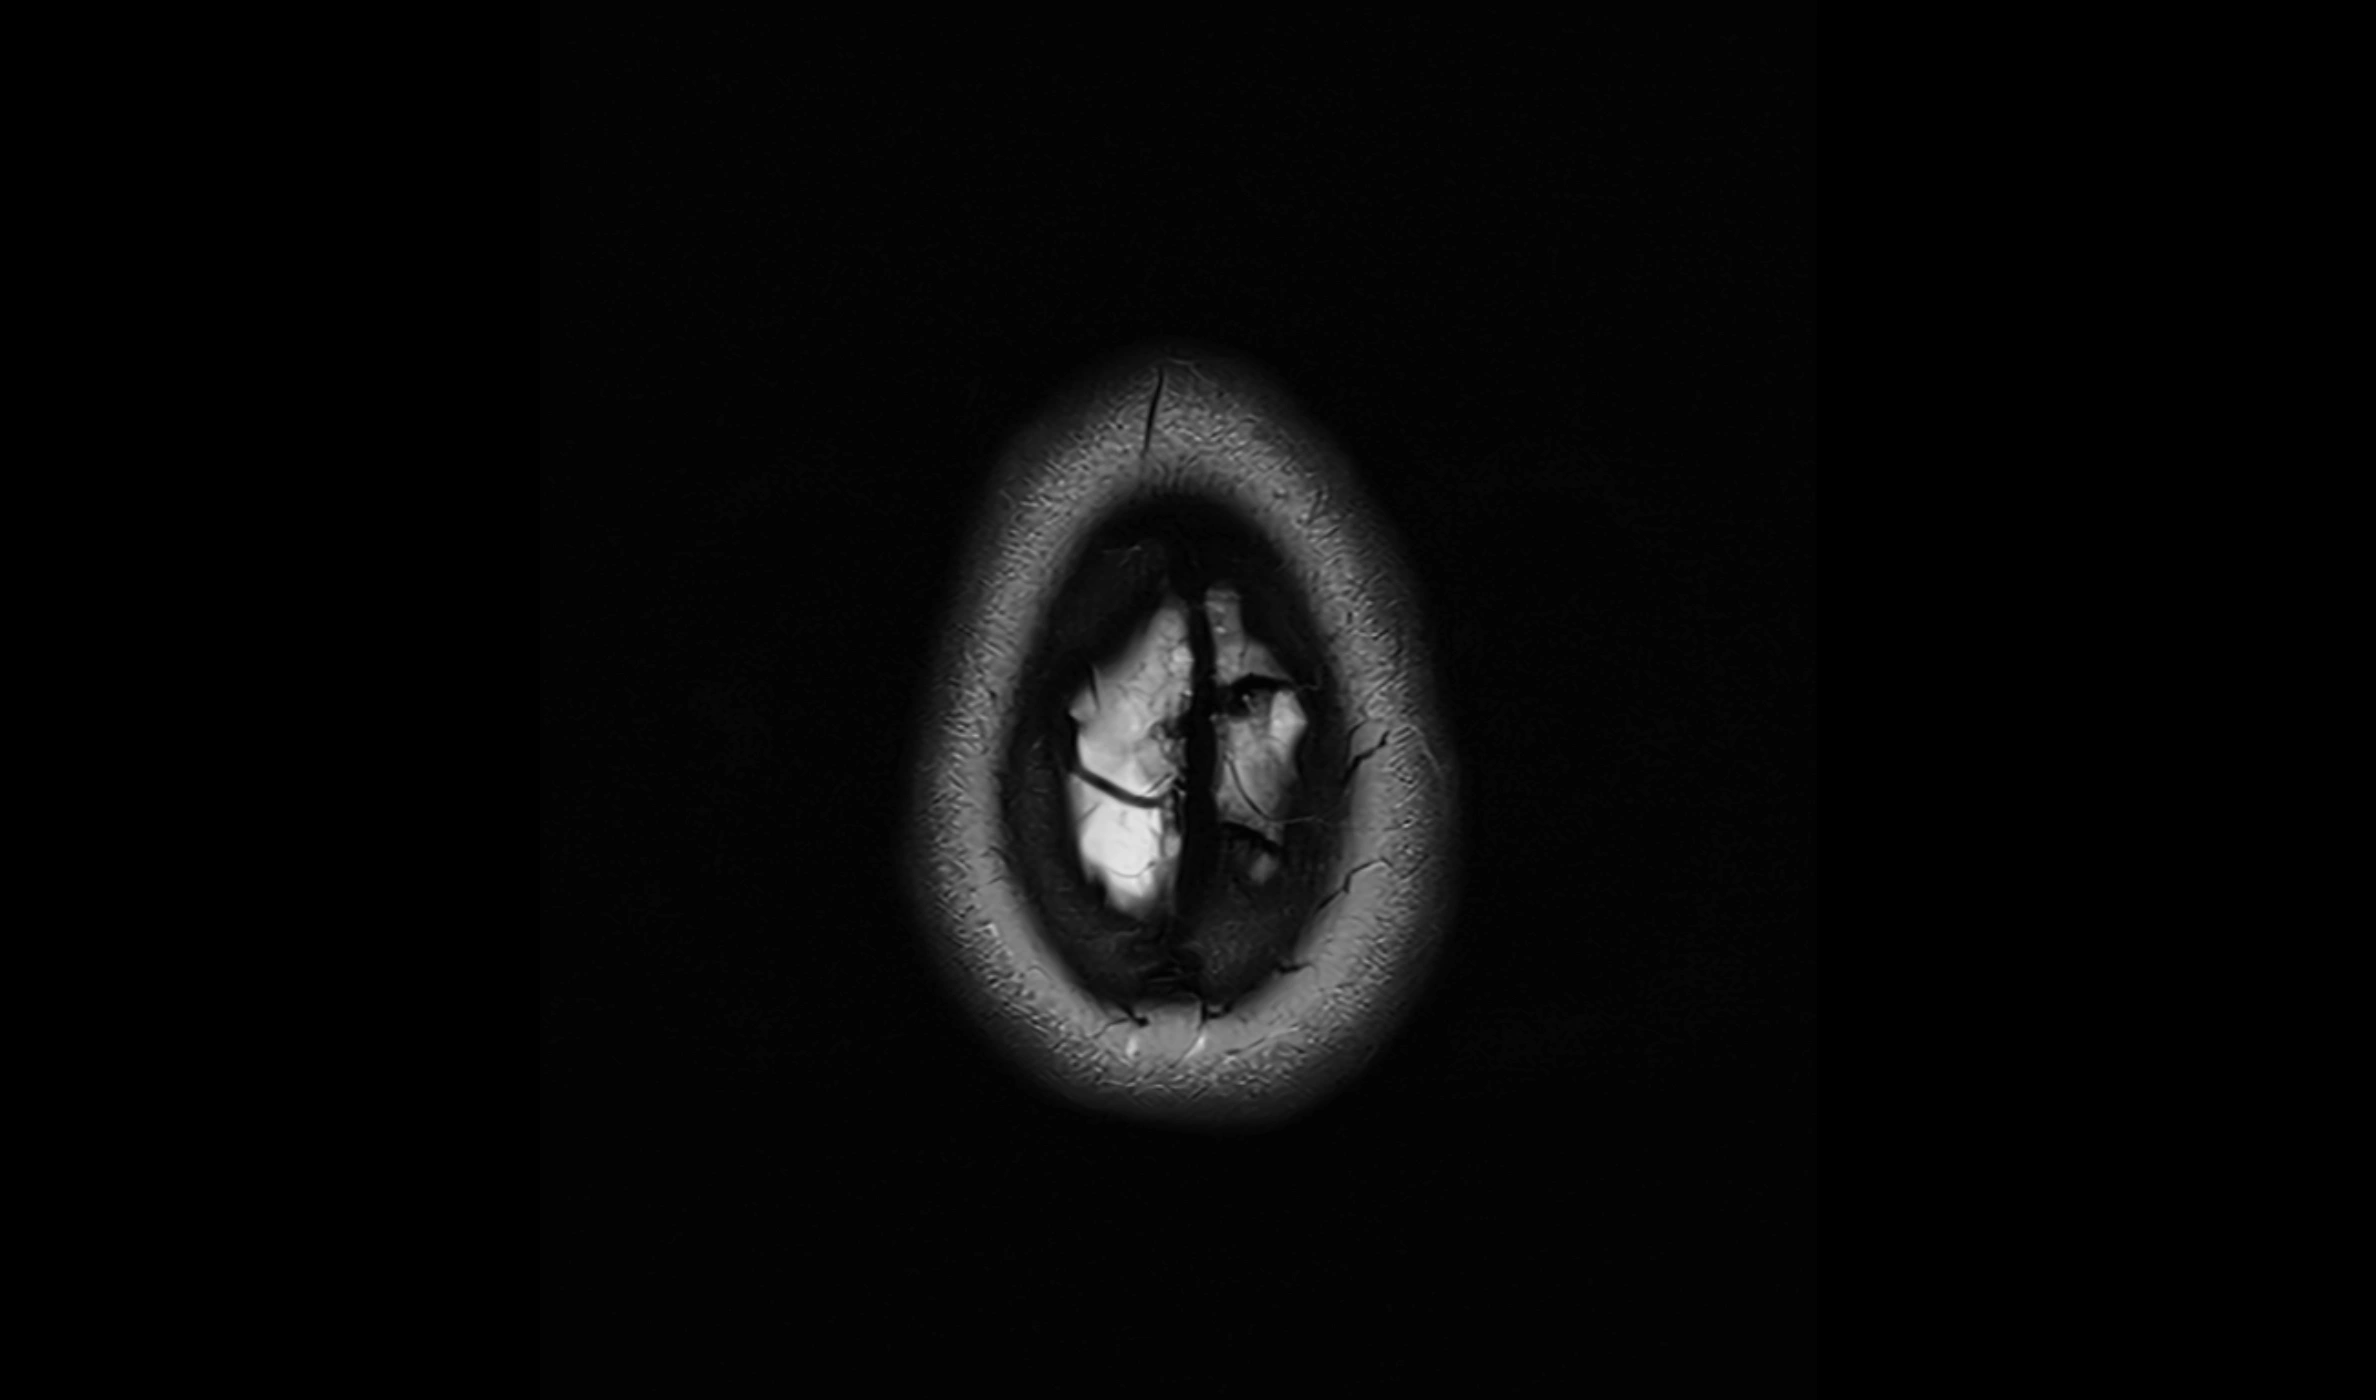

CT image

image